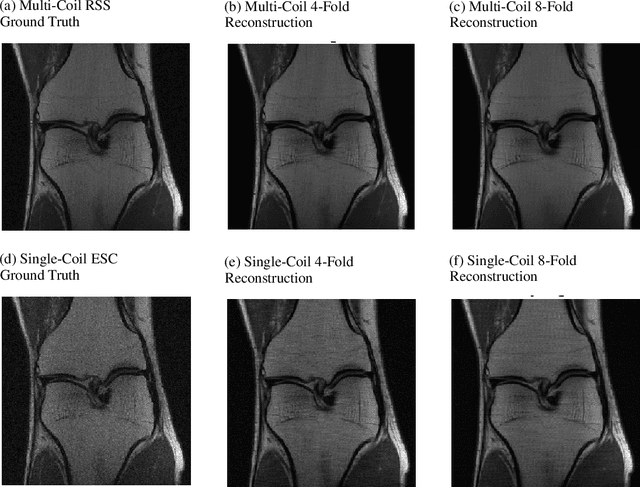

Abstract:Iterative learning to infer approaches have become popular solvers for inverse problems. However, their memory requirements during training grow linearly with model depth, limiting in practice model expressiveness. In this work, we propose an iterative inverse model with constant memory that relies on invertible networks to avoid storing intermediate activations. As a result, the proposed approach allows us to train models with 400 layers on 3D volumes in an MRI image reconstruction task. In experiments on a public data set, we demonstrate that these deeper, and thus more expressive, networks perform state-of-the-art image reconstruction.

Abstract:We, team AImsterdam, summarize our submission to the fastMRI challenge (Zbontar et al., 2018). Our approach builds on recent advances in invertible learning to infer models as presented in Putzky and Welling (2019). Both, our single-coil and our multi-coil model share the same basic architecture.